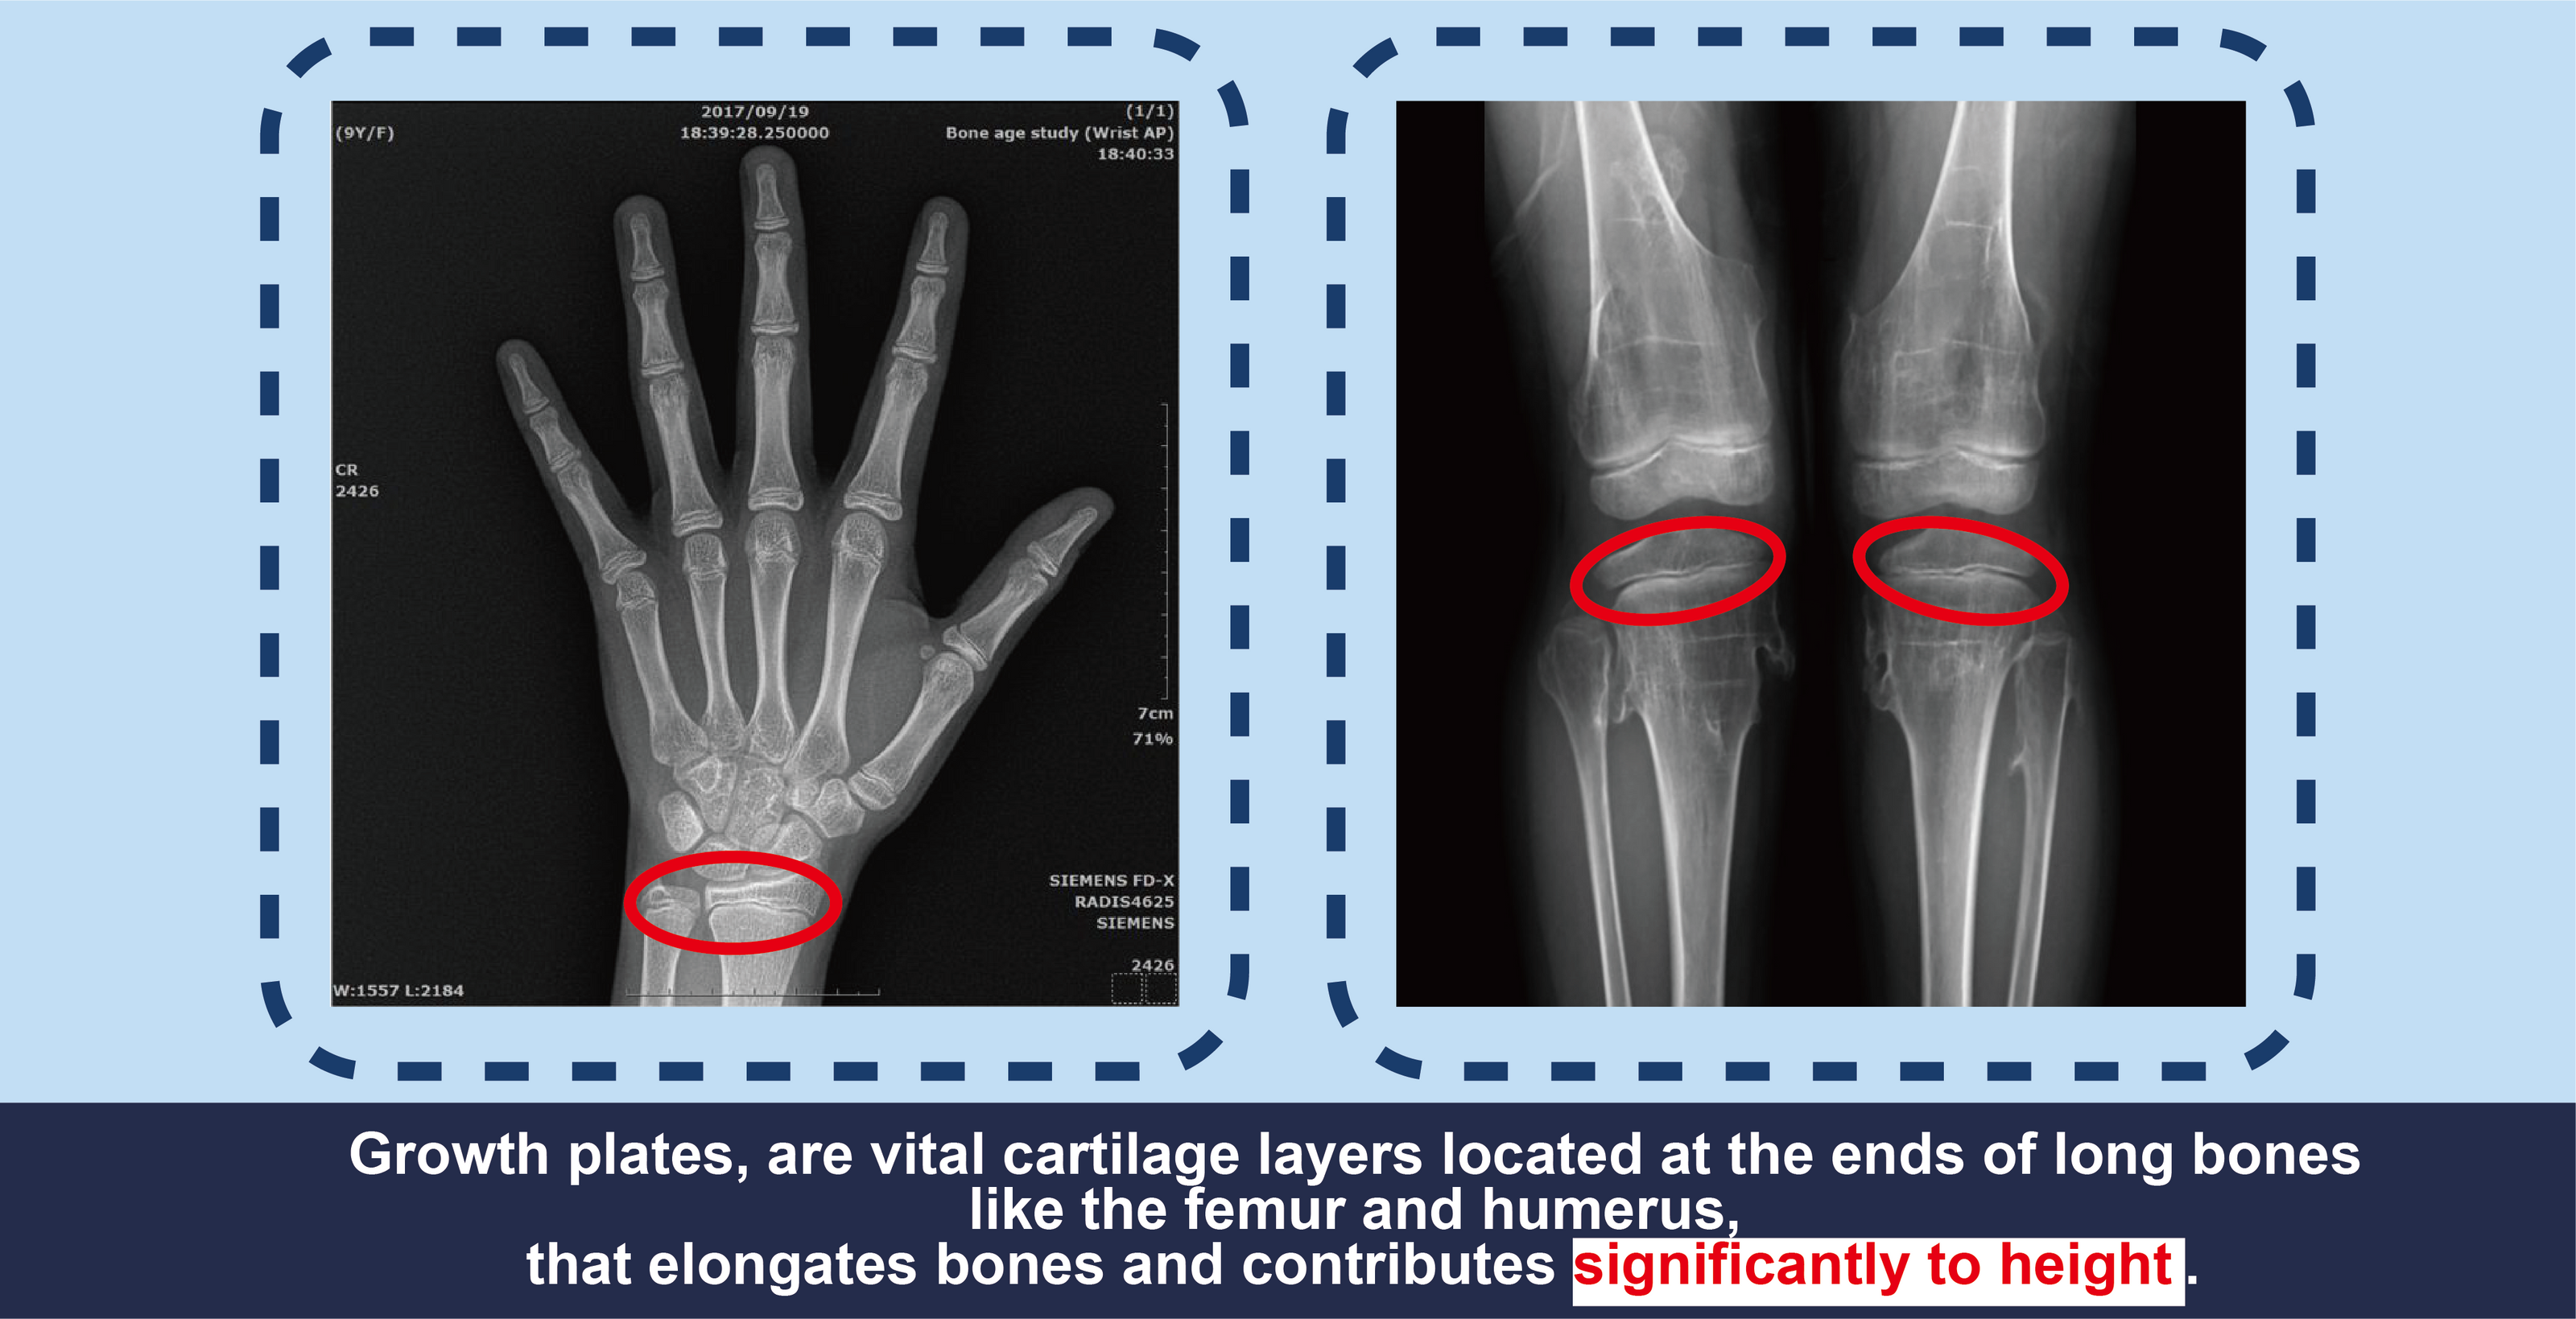

Growth plates, or epiphyseal plates, are vital cartilage layers located at the ends of long bones like the femur and humerus. These plates are highly active sites of cell division and growth, forming new bone tissue that elongates bones and contributes significantly to height. Before puberty, growth plates drive rapid height increases through their active cellular processes, making them central to adolescent skeletal development.

The condition and timing of growth plate closure are key determinants of final height. Below, we delve into the science of growth plates and their influence on height.